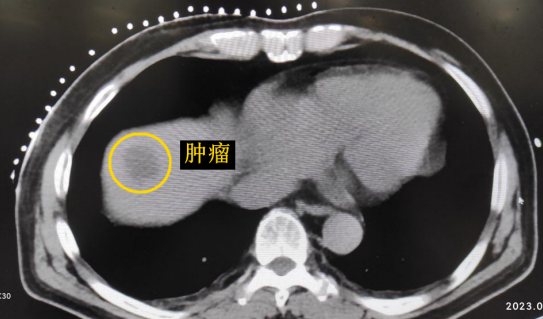

經(jīng)過多學(xué)科討論,陳寶瑩主任根據(jù)影像資料指出,患者轉(zhuǎn)移瘤位于腹膜后,內(nèi)側(cè)瀕臨人體最大的血管——主動脈;前方同樣有血管緊貼腫瘤;外側(cè)是腎臟,后方是椎體和神經(jīng),夾縫中進(jìn)針難度大,治療時(shí)要避免周圍重要臟器、血管和神經(jīng)的損傷,因此可以選擇CT引導(dǎo)下精準(zhǔn)穿刺活檢同步冷凍消融治療,即獲得病理組織有利于下一步全身治療方案的調(diào)整,同時(shí)殺死腹膜后轉(zhuǎn)移瘤,周圍正常組織損傷的可能性也小。

患者老年男性,曾于2021年行結(jié)腸癌手術(shù)。幾月前,發(fā)現(xiàn)肝臟轉(zhuǎn)移瘤,但沒有干預(yù)。近期CT顯示該轉(zhuǎn)移瘤明顯增大,并發(fā)現(xiàn)另一處轉(zhuǎn)移灶。

影像診療科陳寶瑩主任團(tuán)隊(duì)評估后指出,較大的腫瘤位于肝頂部緊貼膈肌,如果繼續(xù)發(fā)展,腫瘤很可能突破肝包膜侵犯到膈肌,建議及時(shí)干預(yù)。病變緊臨膈肌,如果要完全消融,膈肌損傷的可能性就比較大,與其他局部治療方式比較,冷凍消融對周圍臟器、血管及神經(jīng)損傷的可能性較小、安全性更高、患者疼痛感較輕,建議通過CT精準(zhǔn)引導(dǎo)下經(jīng)皮微創(chuàng)冷凍消融治療。

CT精準(zhǔn)定位腫瘤